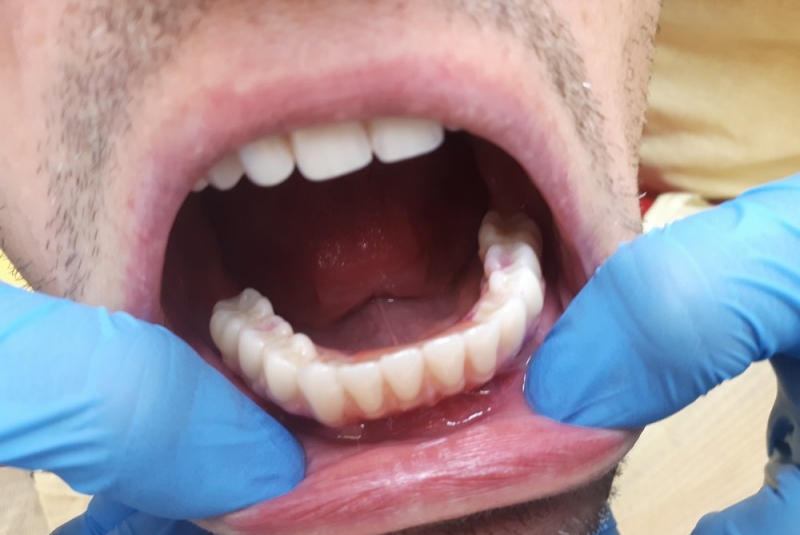

- TN- totálna náhrada

Totálna implantologická náhrada zubov v dolnej čeľusti